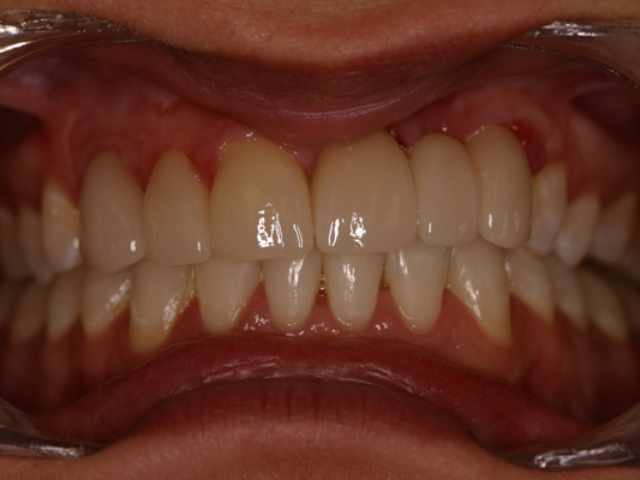

Case Study 14

Problem: This young man was hit by a car while riding his bike. He had multiple fractures in his jaw and three front teeth were fractured.

Plan: Our plan… his fractures were fixed. The trauma left a bony defect which was grafted as well as soft tissue VIP grafts. Placed three separate implants with guided surgery. Molded the tissue and placed Zirconium abutments with porcelain crowns.

A great young man with a confident smile.